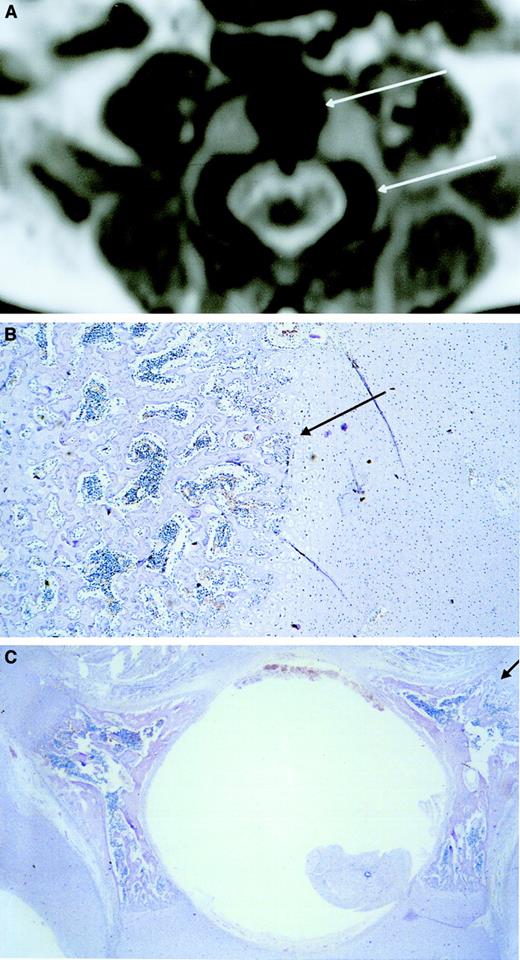

Microscopic histologic sections confirming hematopoietic sites.

(A) Microscopic longitudinal section (4 μm) of the proximal ulna showing the transition between BM and cartilage. Hematopoietic cells were found in the BM area. (B) Microscopic section (4 μm) of a 21-week-old fetal temporal skull showing absence of hematopoiesis. Although desmal and enchondral osteosynthesis has taken place in the temporal skull, no hematopoietic cells are found. Also, the other skull bones did not show hematopoietic cells at these gestational ages. Hematoxylin-eosin staining was used.

Ossification center.

MRI shows low signal intensity (black) in the central area of the vertebral body corresponding to an ossification center (upper arrow). Low signal intensity corresponding to an ossification center is also visible in the lateral area of the vertebral pedicles (lower arrow) (A). Microscopic transversal sections (4 μm) stained with hematoxylin-eosin of the central area of the vertebral body (B) and the lateral areas of the vertebral pedicles (C) show hematopoietic cells between the spiculae, indicating that the low-intensity areas visualized by MRI are hematopoietic areas. The upper and lower arrows in panel A correspond with the arrows in panels B and C, respectively. Original magnification × 40.

To identify the BM hematopoietic sites in the fetus at different gestational ages, total body radiography was performed identifying ossification centers. Corresponding sites were made visible using MRI. The BM compartment could be measured reliably with MRI because differences in signal intensities between cartilage and BM provided the possibility to accurately discriminate these structures in the fetus. To verify that these areas were indeed hematopoietic sites, corresponding histologic sections were made of all these structures. Up to 22 weeks of gestation, hematopoietic cells were detected in all bones except the calvarial bones (skull). Only after 22 weeks of gestation a few hematopoietic cells could be detected in histologic sections, suggesting the beginning of hematopoiesis in the calvarial bones. The absence of hematopoietic cells in the calvarial bones can be explained by the fact that in the frontal and parietal skull bones osteogenesis does not develop from cartilage but takes place through intramembranous ossification. This apparently occurs later in development than enchondral ossification. The connective tissue in which intramembranous ossification occurs and the ossification centers containing the BM compartment in other bones were shown to have the same intensity using MRI. This initially suggested that all these bones belonged to the hematopoietic BM compartment. Based on the histologic analysis, however, the calvarial bones were excluded from addition to the BM compartment. All other bones including the other skull bones have enchondral osteogenesis22 and do develop from cartilage. In these bones cartilage could be easily distinguished from BM using MRI because of the different intensity.